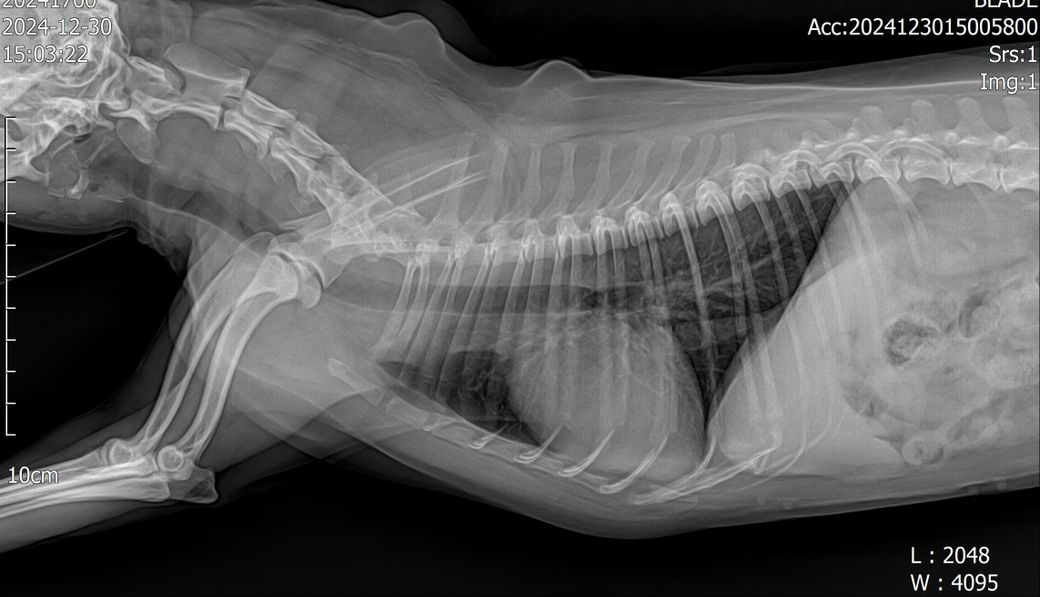

안녕하세요14살 강아지 입니다 6개월전 폐 엑스레이와 현재엑스레이인데요 6개월전 찍었을시 첫병원은 폐섬유화진행중이라고하 두번째병원에선 다르게 만성기관지염이다 했어요

위에사진이 6개월전입니다